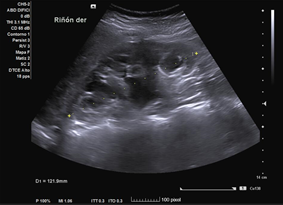

En ecografía clínica desde el centro de salud, se objetiva gran dilatación del sistema excretor del riñón derecho, con adelgazamiento de la cortical (hidronefrosis grado III-IV). No se aprecia litiasis u otra causa obstructiva a nivel renoureteral ni vesical. Riñón derecho conserva tamaño normal. Riñón izquierdo de tamaño y ecoestructura normales, sin dilatación piélica. Vejiga bien replecionada sin alteraciones en su pared.

Juicio Clínico: Riñón derecho con dilatación de su sistema excretor.

Concordancia con el hospital. Se realiza Urografía por Tomografía Computada que confirma hidronefrosis grado IV en riñón derecho; no se objetivan litiasis renoureterales; se aprecia arteria accesoria polar inferior de dicho riñón, la cual cruza la unión pieloureteral ipsilateral.